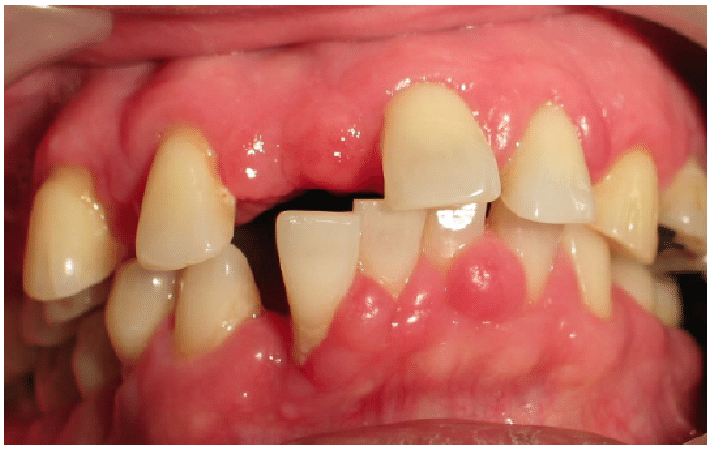

🔴IDIOPATHIC GINGIVAL ENLARGEMENT

-Affects the attached gingiva as well as the gingival margin and interdental papilla

-Involvement is limited to the either jaw

-Enlarged gingiva is pink, firm and almost leathery in consistency

-Characterstic minutely pebbled surface